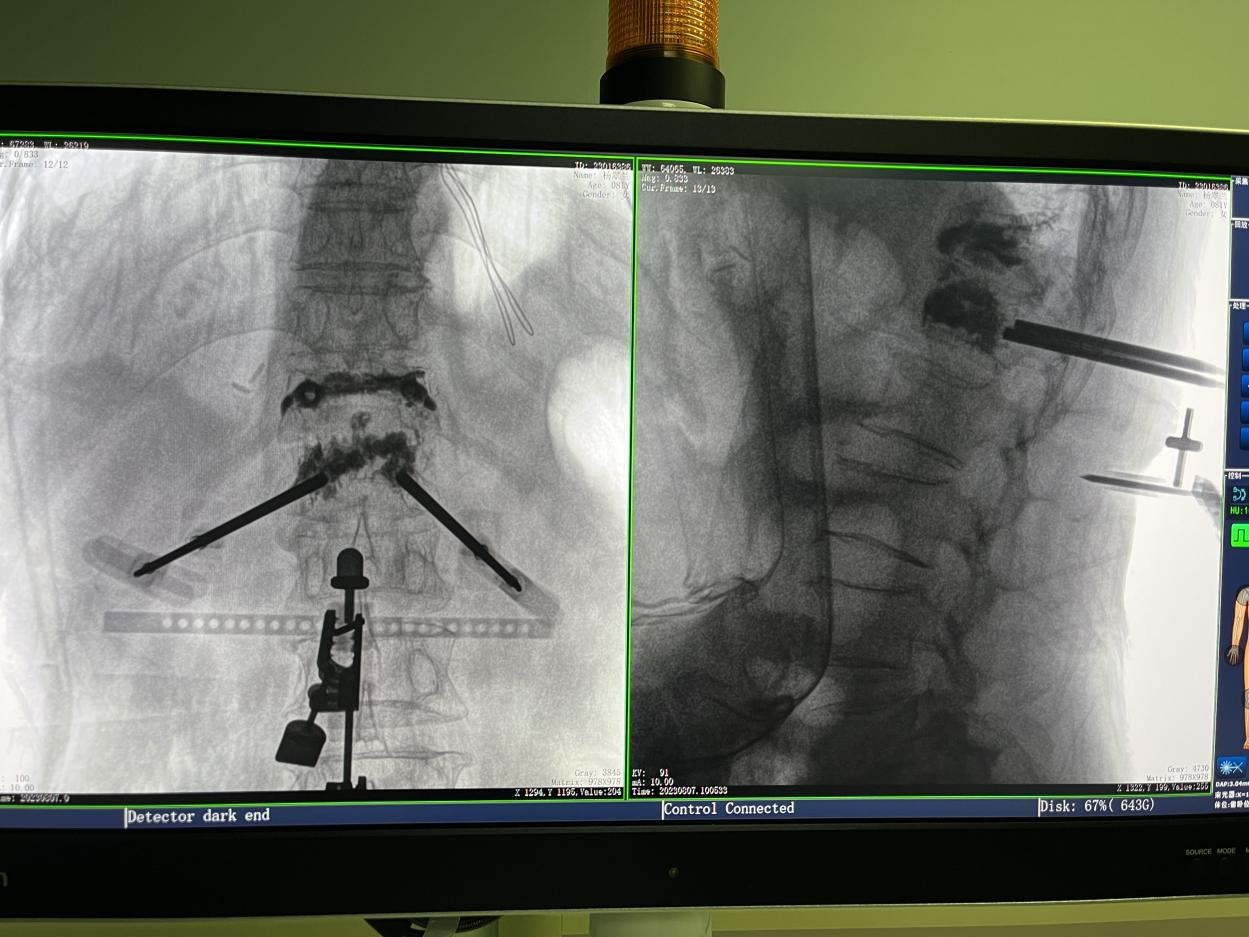

PL300B搭配普愛(ài)醫(yī)療自主研發(fā)生產(chǎn)的平板三維C形臂使用,通過(guò)三維立體術(shù)中圖像,手術(shù)醫(yī)生可從各個(gè)方位觀察合適的手術(shù)入路,并進(jìn)行關(guān)鍵數(shù)據(jù)測(cè)量,從而最大限度地避開(kāi)危險(xiǎn)區(qū)。

骨科機(jī)器人手術(shù)-術(shù)中影像